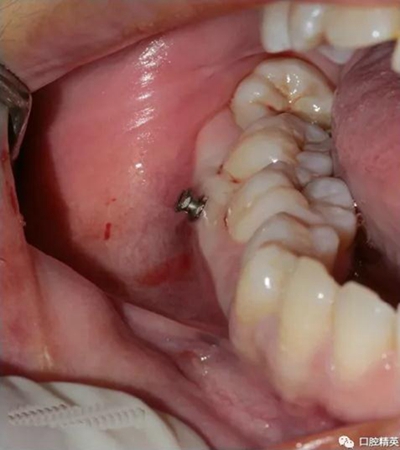

一般情況下是成年人使用,特殊病例十三、四歲的小孩可以用。種植釘可以打在牙槽骨的任何部位??梢栽?個(gè)牙齒之間的牙槽骨上打釘,或者打在頰側(cè)牙槽骨與牙根之間,主要看你是如何應(yīng)用支抗了。2個(gè)牙齒之間的牙槽骨上打釘,支抗作用拉動(dòng)的牙齒有限,而打在頰側(cè)牙槽骨與牙根之間可以將整個(gè)牙列拉向遠(yuǎn)中移動(dòng)。種植支抗釘在矯正結(jié)束后要拿下來(lái)。

再次,植入微型種植體,在附著牙齦處不需要粘骨膜翻瓣,在牙槽黏膜處則需要切開(kāi)黏膜以避免植入時(shí)軟組織被卷入,植入部位通常在膜齦結(jié)合部位或偏根方2~3mm,植入角度與骨面垂直并傾斜15~20度,即向根尖方向植入,術(shù)后拍根尖片以確認(rèn)與牙根的關(guān)系。術(shù)后口服抗生素預(yù)防感染并進(jìn)行口腔衛(wèi)生宣教。

5 、常見(jiàn)失敗原因:感染;旋轉(zhuǎn)螺絲刀幅度過(guò)大;排斥反應(yīng);軟組織夾入;骨質(zhì)疏松;使用時(shí)力值過(guò)大。

6 、常見(jiàn)術(shù)中和術(shù)后并發(fā)癥:損傷牙根或牙周膜;種植釘斷裂;感染;種植釘松動(dòng)(松動(dòng)率:約10%,下頜大于上頜)